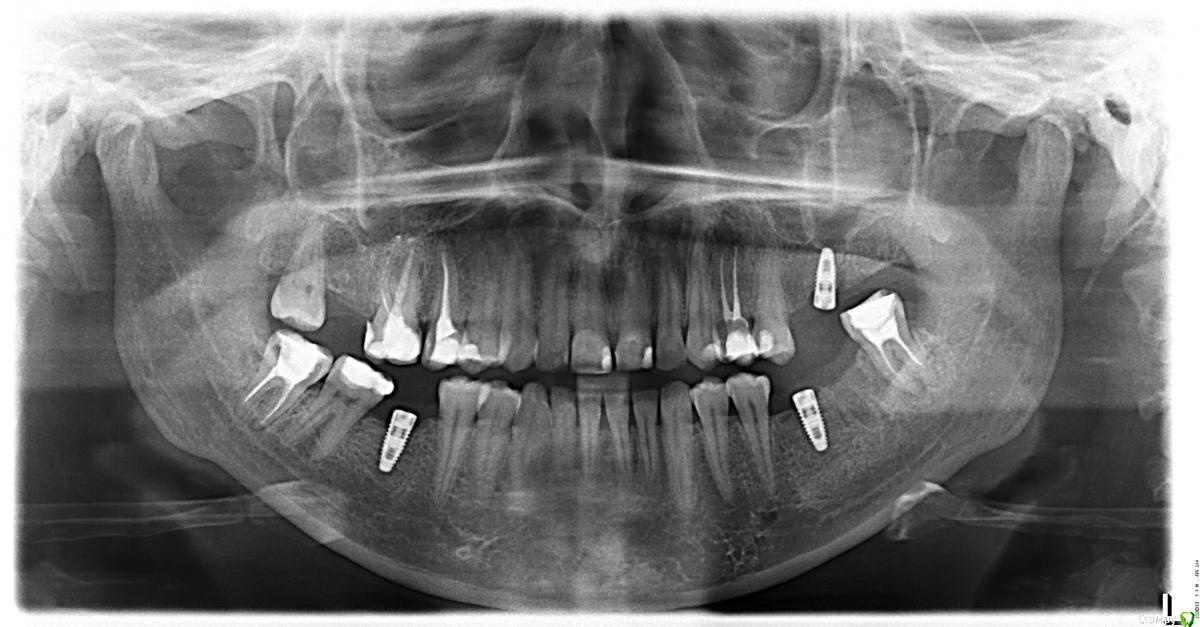

Madira Опубликовано 14 марта, 2016 Автор Поделиться Опубликовано 14 марта, 2016 (изменено) Здравствуйте. Сделала панорамный снимок. Что-то меня он очень сильно смущает по всем 3м имплантам, но я не специалист. Изменено 14 марта, 2016 пользователем Madira Ссылка на комментарий

Madira Опубликовано 14 марта, 2016 Автор Поделиться Опубликовано 14 марта, 2016 (изменено) Простите что снимок в перевернутом виде, на компе он отображается нормально. UPD. все исправила. Изменено 14 марта, 2016 пользователем Madira Ссылка на комментарий

diesel87 Опубликовано 14 марта, 2016 Поделиться Опубликовано 14 марта, 2016 Интересно было бы посмотреть снимки после установки имплантов, может у доктора метода работы такая. Ссылка на комментарий

Madira Опубликовано 14 марта, 2016 Автор Поделиться Опубликовано 14 марта, 2016 Сразу после установки снимки не делались. Врач сказала, что сделает перед установкой фдм. Что можно сказать по сегодняшним снимкам? Что-то плохое увидели?(( Импланты nobel. Ссылка на комментарий

4ebstom Опубликовано 16 марта, 2016 Поделиться Опубликовано 16 марта, 2016 По собственному опыту могу сказать если имплант "не приживается"-понятно в течении 2-3 недель.После 2 х месяцев случаев "отторжения " не было.Встречались так называемые "заглушечные" свищи-симптомы проходят после ревизии и установки формирователя.На снимке,который Вы выложили,видно отсутствие кости около шеек имплантов.Часто такие импланты при наличии обьема десны служат неплохо(если процесс стабилизировался и нет воспаления).Желаю Вам благополучного решения этого вопроса. Ссылка на комментарий

diesel87 Опубликовано 16 марта, 2016 Поделиться Опубликовано 16 марта, 2016 То же что и по снимку, резорбция кости по шейке имплантатов. И так же, судя по нему, скорее всего нижние 2 импланта не были установлены вровень с костью, скорее всего на 0,5-1,0 мм над уровнем кости. С установкой фдм возможно картина станет лучше, отдохните пока, погуляйте 3-4 недели с ними, мягкие ткани должны успокоиться. Ссылка на комментарий